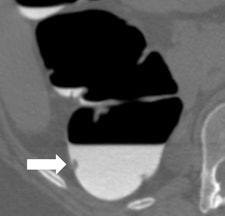

Along with his colleague Dr. Stefaan Gryspeerdt, Lefere has addressed CTC's potential pitfalls in a comprehensive paper published online January 4 in Insights into Imaging. Their top tips are to perform state-of-the-art CTC (preparation based on fecal tagging, along with colonic distension with CO2 plus injector, dual positioning, and smooth muscle relaxation), remember the general principles of interpretation, and take special care when examining the rectum and caecum.